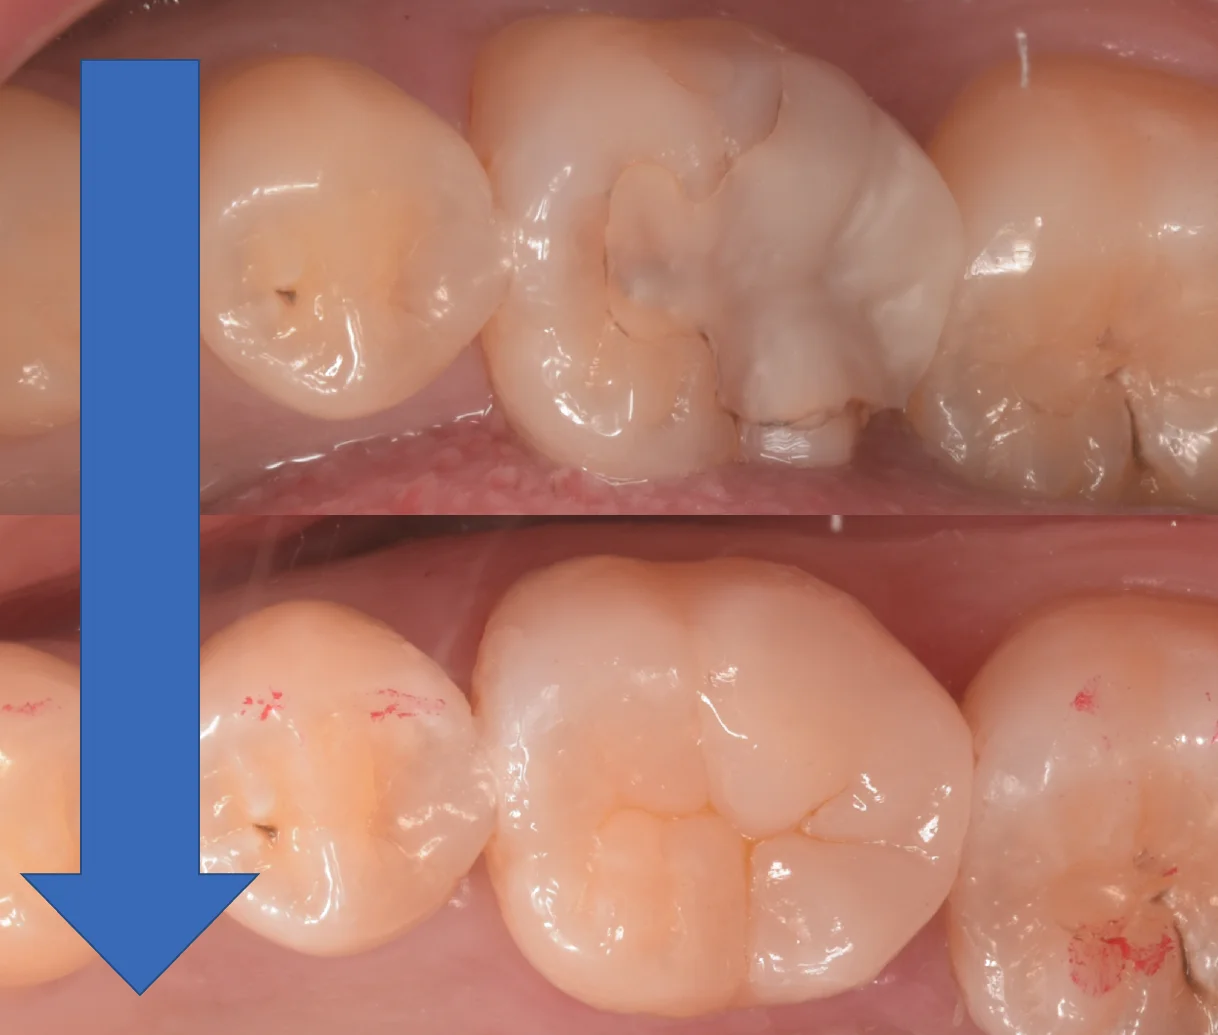

術前術後の写真がこちらです。

遠方から長時間の治療、お疲れ様でした!

なるべく長く使えるといいですね!

定期検診でしっかりと研磨することでツヤや汚れのつきにくさをキープすることができますので、ぜひしっかりと定期検診にお越しください!

また歯科医師の方ですからご存知だとは思いますが、TCHをはじめとした力のコントロールに不備があるとありとあらゆる治療がもたなくなりますので、その点もご注意くださいね!